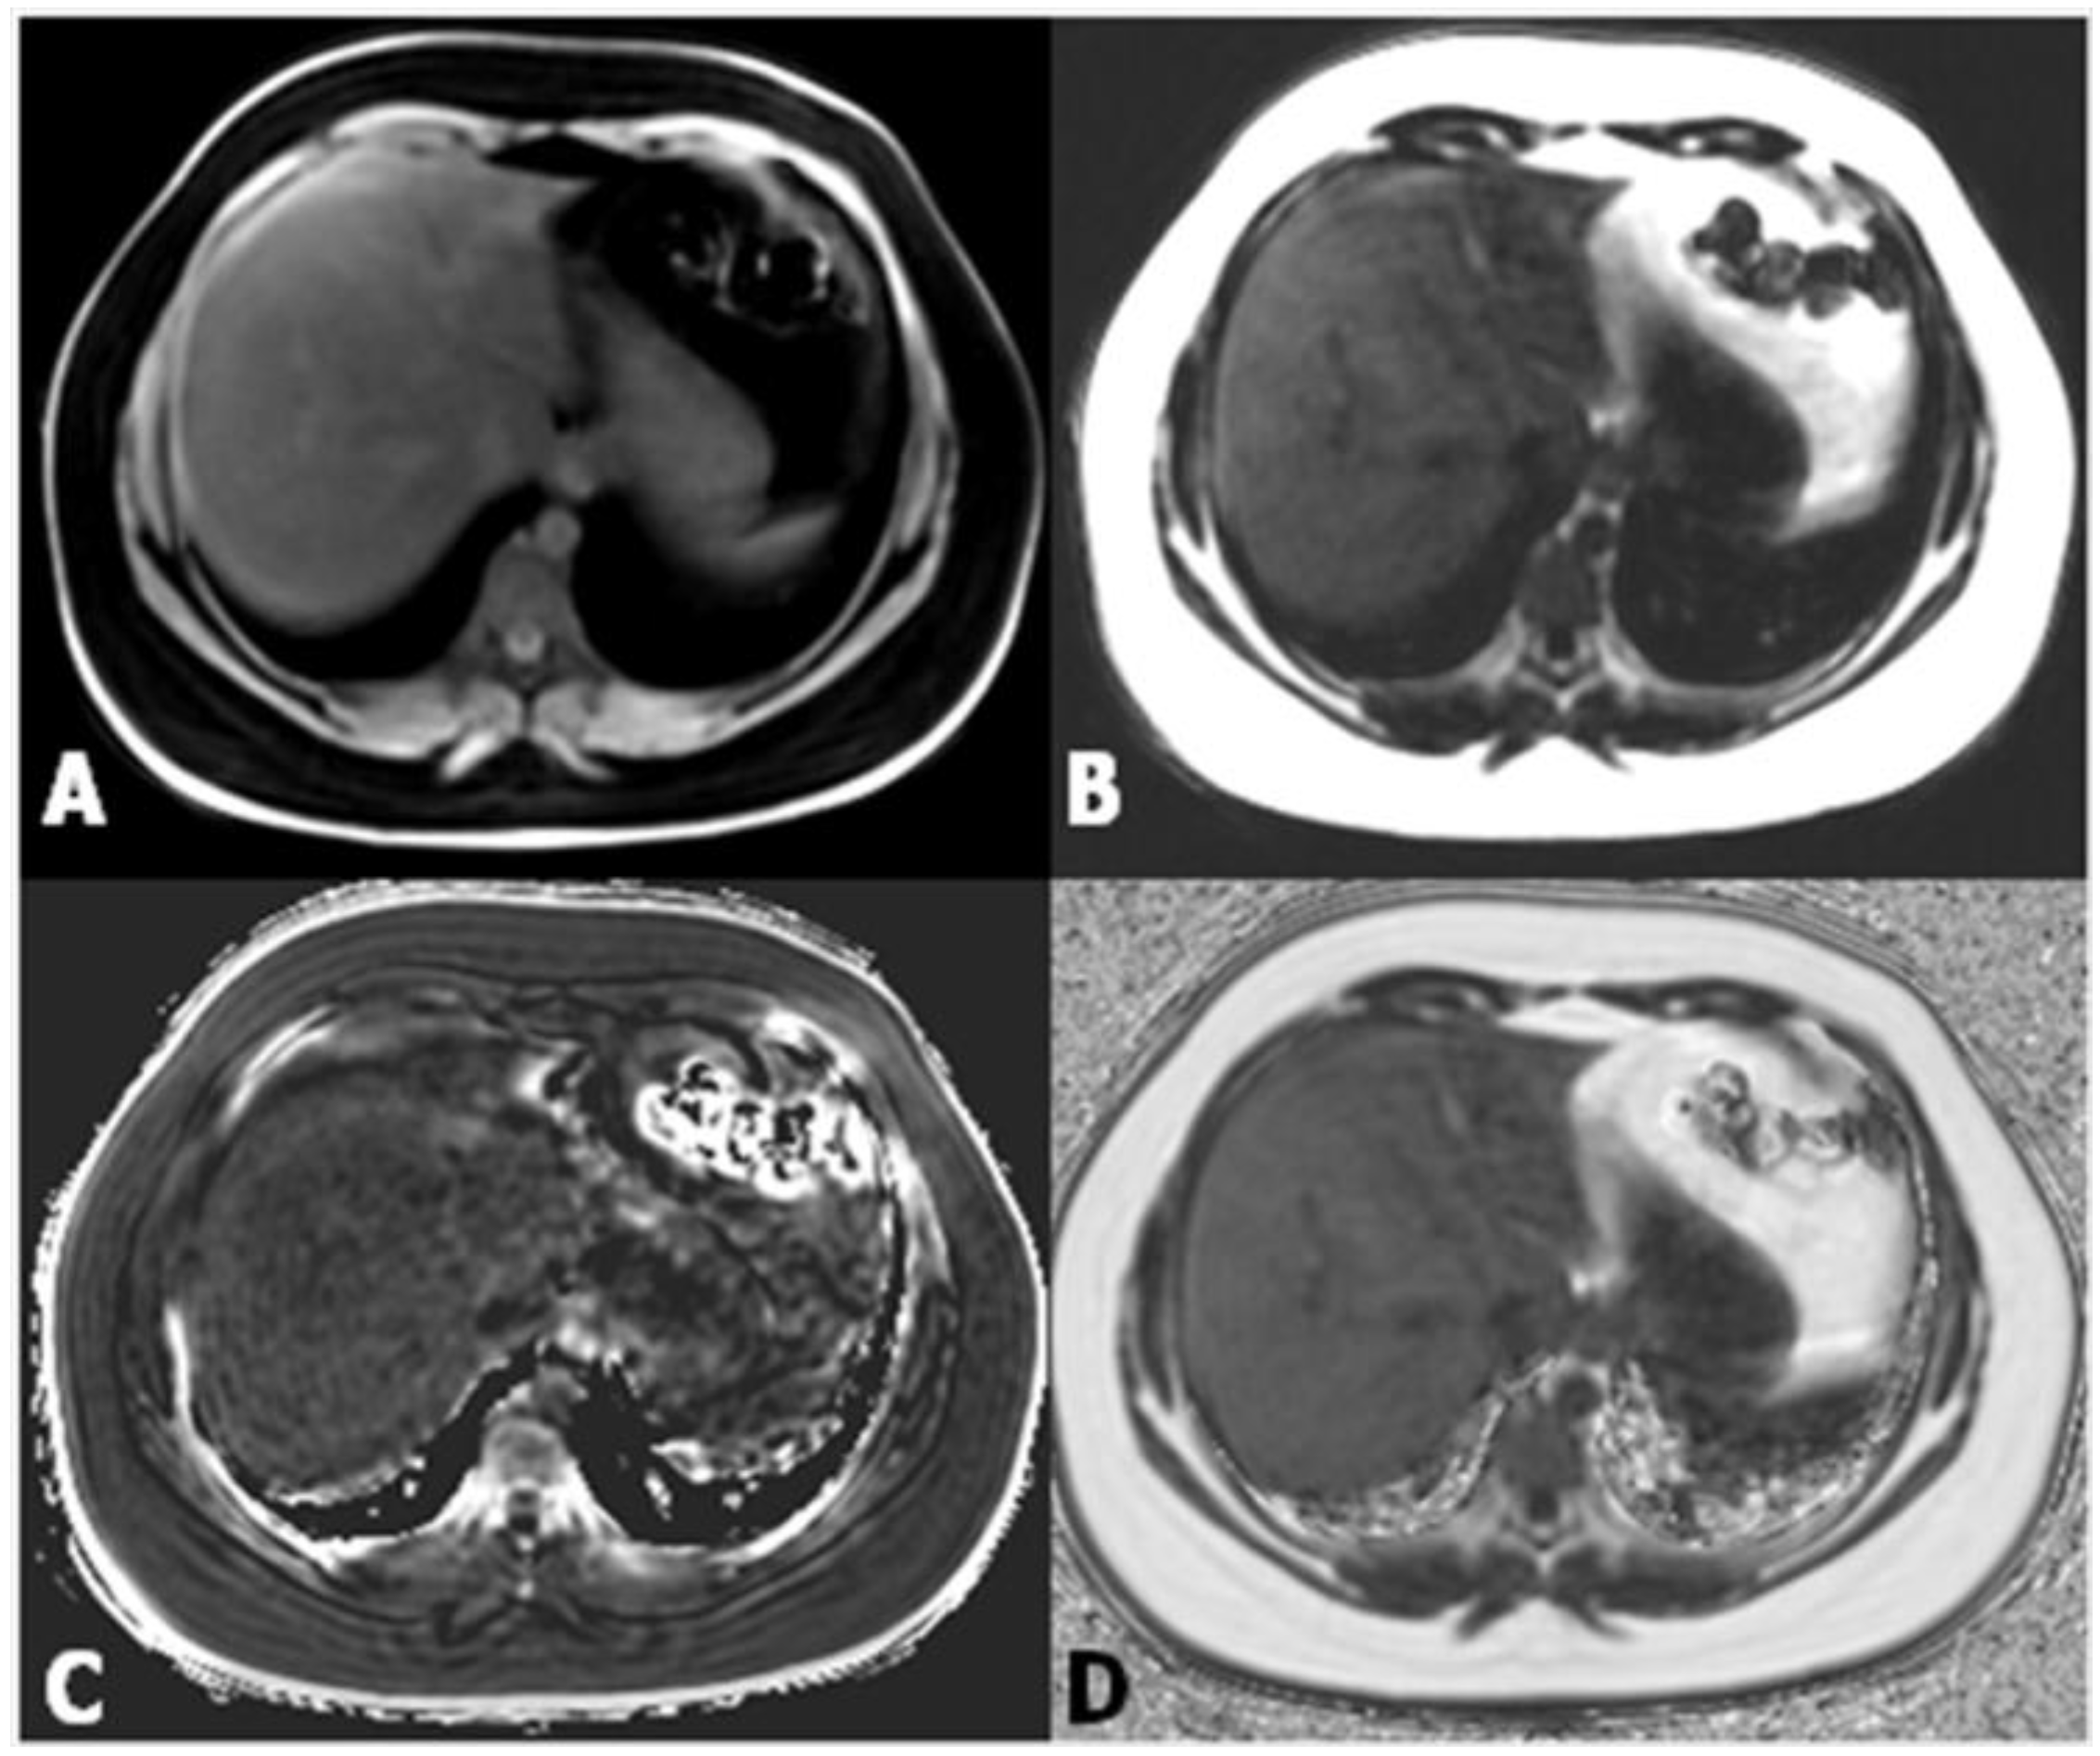

Proton density fat fraction (PDFF) measurement by MRI appears to be the most objective test for the quantification of liver steatosis, and has been recently adopted as a standard reference in clinical trials [17,18]. This technique overcomes the limits of dual-echo sequence, such as the T2* effect, T1 bias, spectral complexity of fat, eddy currents, noise bias, and magnetic non-homogeneity. PDFF is the ratio of density of mobile lipid protons (primarily triglycerides) and the total density of protons from water and fat. Moreover, it shows objective fat quantification and grading similar to magnetic resonance spectroscopy (MRS) in a single breath-hold, and measurement is easily performed by drawing a region of interest (ROI) on an automated PDFF map (Figure 4) [19].

Figure 4.

(A,B) Images from datasets acquired from a multi-echo, low flip angle sequence with clear separation of fat from nonfat tissue; (C) the R2 image is useful in the evaluation of iron concentration; (D) the fat-fraction image allows one to easily obtain the fat percentage by drawing a region of interest (ROI) within the parenchyma.

Above all, it is very easy and practical for fat fraction measurement. In pediatric patients, comparison of biopsy and PDFF has shown promising results [20]. PDFF is an unconfounded and fundamental property of tissue, and it is insensitive to changes in acquisition parameters, thereby making it a robust quantitative biomarker [21]. PDFF is uniform across scanner platform and manufacturer and even field strength, and can standardize MRI-based fat quantification [22,23]. Moreover, simultaneous calculation of R2* and T2* maps from the same MRI sequence enables the estimation of hepatic iron content, which can be important for the diagnosis of co-existing fatty liver and hepatic iron overload [24,25].